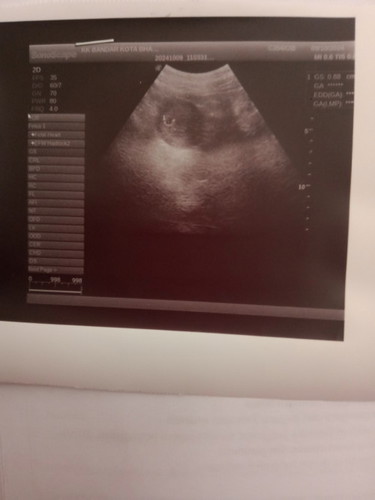

8minggu 2 hari

Sedih rasa harini..doc cek kata kantung saja nampak...2 kli scan tetap xnampak...mungkin sbb masih awal lgi kot...nnti repeat scan 12 minggu plk..semoga ad keajaiban nnti... sedih sangat sy rasa😌

nampak macam ada yolk sac tu dalam kantung